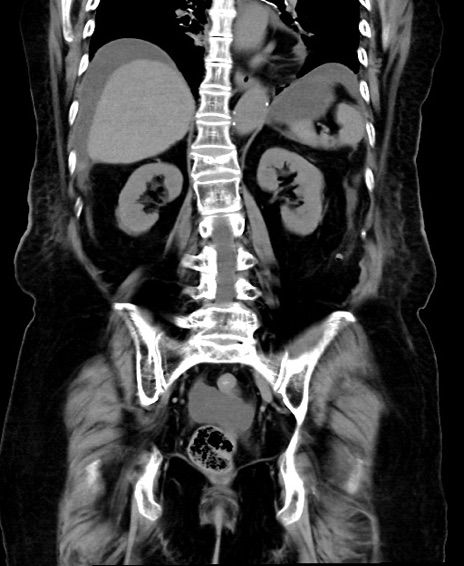

冠状断像